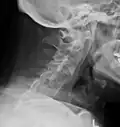

Lateral X-ray of the mid back in ankylosing spondylitis -

Lateral X-ray of the neck in ankylosing spondylitis -